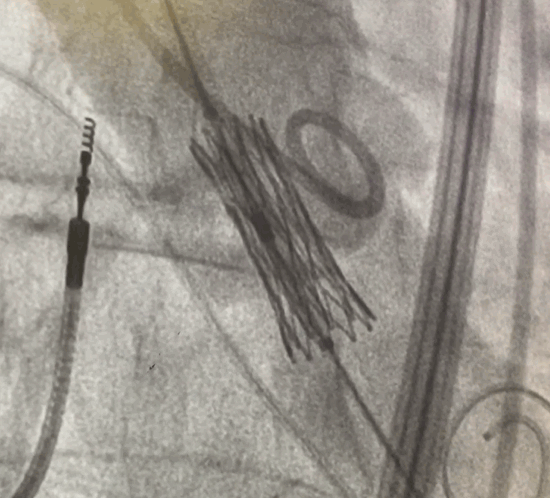

A replacement valve expands inside a patient's aorta at RGH.